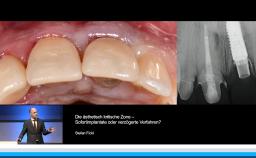

Implantatverlust mit Defektsituation: Erneute Implantation oder Alternativtherapie?

Dieter Weingart

Basierend auf diversen Studien und eigener klinischer Erfahrung stellt Dieter Weingart seine Erkenntnisse und Schlussfolgerungen zum Thema Implantatverlust mit Defektbildung vor. Er illustriert das Thema mit eigenen klinischen Fällen inklusive Langzeit-follow-ups.